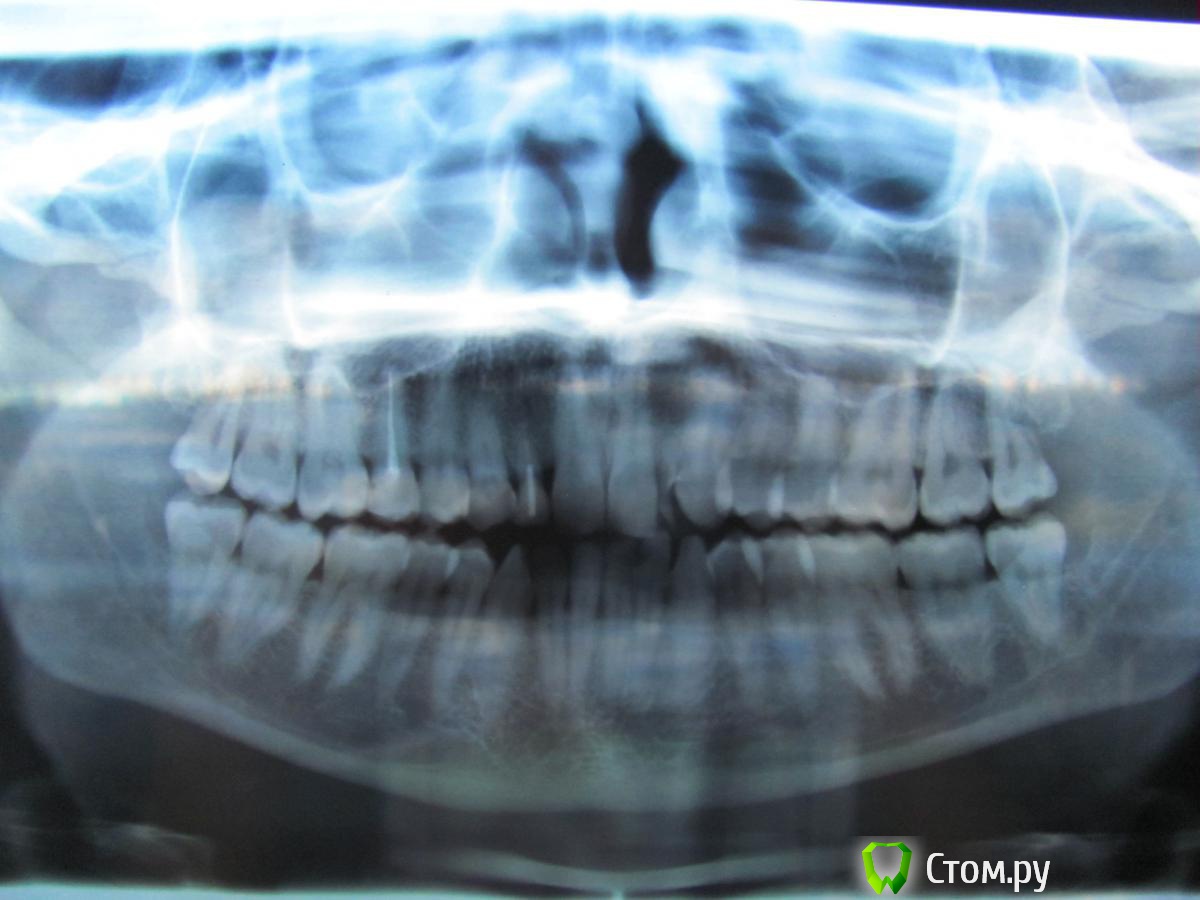

broxi Опубликовано 1 октября, 2014 Поделиться Опубликовано 1 октября, 2014 У меня молочные двойки, которые в 18 лет первый раз отреставрировала. Потом они отваливались периодически из-за неправильного прикуса. Сейчас мне 32 года. И вот отвалилась правая двойка. Возможности реставрировать, говорят, нет. Корешок совсем маленький, не за что зацепиться. Места под имплантат нет. Предлагают 1,5-2 года поносить брекеты, расширить место и вставить имплантат. Заодно то же самое проделать с левой двойкой, которая тоже рано или поздно отвалится. Вроде бы тройки-клыки тоже молочные, но они никогда не реставрировались и выглядят более устойчивыми. Но если носить брекеты, они вряд ли выживут. Получается 4 имплантата. Указанный выше вариант для меня пока крайне нежелателен. Какие есть еще возможности? Я подумываю над тем, чтобы просто удалить обломившуюся двойку. Подвинется ли со временем тройка-клык на место этой двойки естественным образом? Или может ей как-то помочь… Клык у меня не совсем похож на клык, сильно закругленный книзу. Может, ничего будет смотреться? За "голливудской улыбкой" не гонюсь, хочется по-максимуму сохранить свои зубы и избежать брекетов и имплантатов. Можно еще потом замаскировать клык под резец или винир поставить? Ссылка на комментарий

SDC Опубликовано 1 октября, 2014 Поделиться Опубликовано 1 октября, 2014 Если Вы всеми силами избегаете врача-ортодонта и брекеты, то на мой взгляд, лучшим выходом будет протезирование молочных клыков консольными протезами (боковые резцы - консоли), с удалением корней молочных резцов.Когда клыки выйдут из строя, провести одномоментную имплантацию в области клыков и повторить те же консольные протезы. Ссылка на комментарий